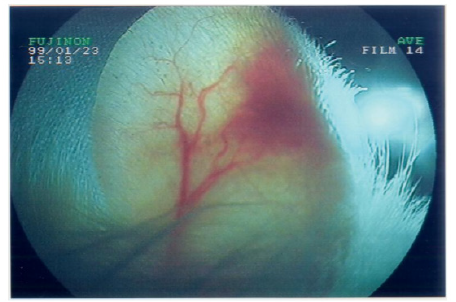

A. Trans-illumination of the ear pavilion implantation site with a fiberscope FUJINON light source

Such an implant was able to contractile activity different from the host one (much slower: 70-80 instead of 350-450 beatings/ min), as revealed by ECG registration (Figure 4A). It was also able to ensure blood flow through it, as shown by USI and MRI investigations (Figure 4B)(Figure 4C).At the ear site, as shown in our early investigations, the implant evolution of the foetal heart implant was the following: during the first week “regression” to a mass of necrotic cells (infarct), undifferentiated cells and foetal erythrocytes among which some living cardio-myoblast were observed (Figure 5A)(Figure 5B). During the following 3-4 weeks a ventricle-like formation with normal cardio-myocytes developed and was able to have a normal function i.e. electrical activity modified by adrenergic and vagal influences, contractions able to propel blood through the cavities and ensure a blood flow assessed either by USI and MTI investigations (Figure 4B)(Figure 4C) [29, 30]. In late delays, after 8 months post-surgery, the progressive replacement of myocytes by adipocytes was noted evoking an aging evolution (Figure 5C) (Figure 5D) (Figure 5E) (Figure 5F) (Figure 5G).